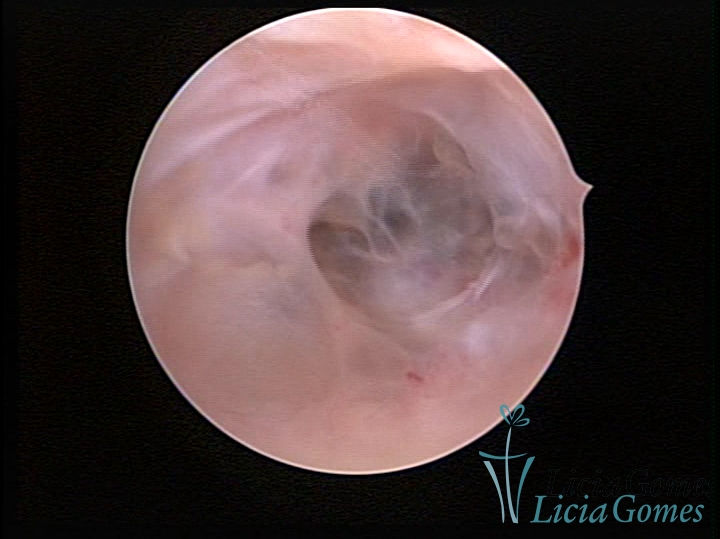

• SINÉQUIA TIPO FIBROMUSCULAR